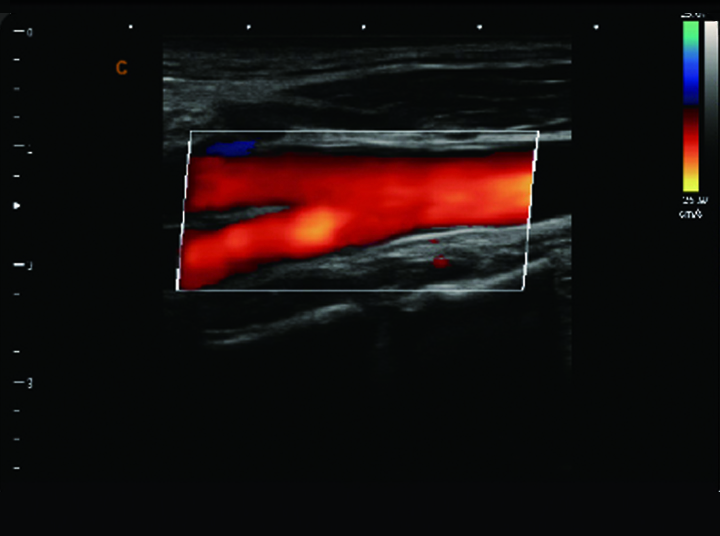

颈动脉,彩色模式